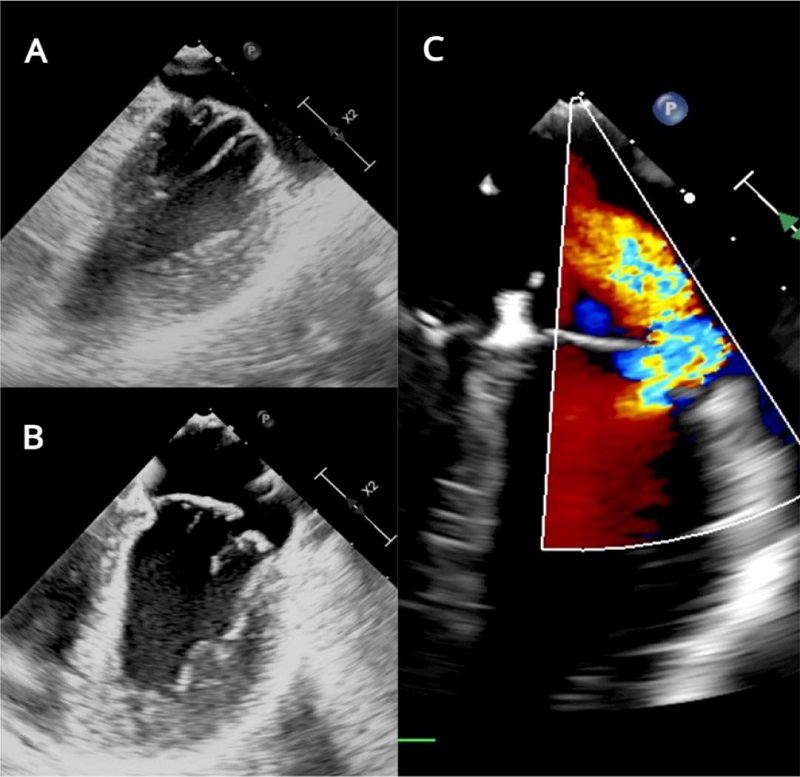

Presence of ostium secundum ASD of 14 mm with left to right shunt (Figure 2). Normal biventricular ejection fraction, enlargement of right cardiac chambers and left atrium, and noticeable MV insufficiency (Figures 3C, 4A, 4B).

MV features included annular dilation, leaflet redundancy, with failure of coaptation between A2-A3 and P2-P3, associated with multisegmental prolapsing/billowing MV components, and thickened, elongated chordae tendineae, typical of Barlow’s disease (BD) (Figures 3A, 3B, 5).